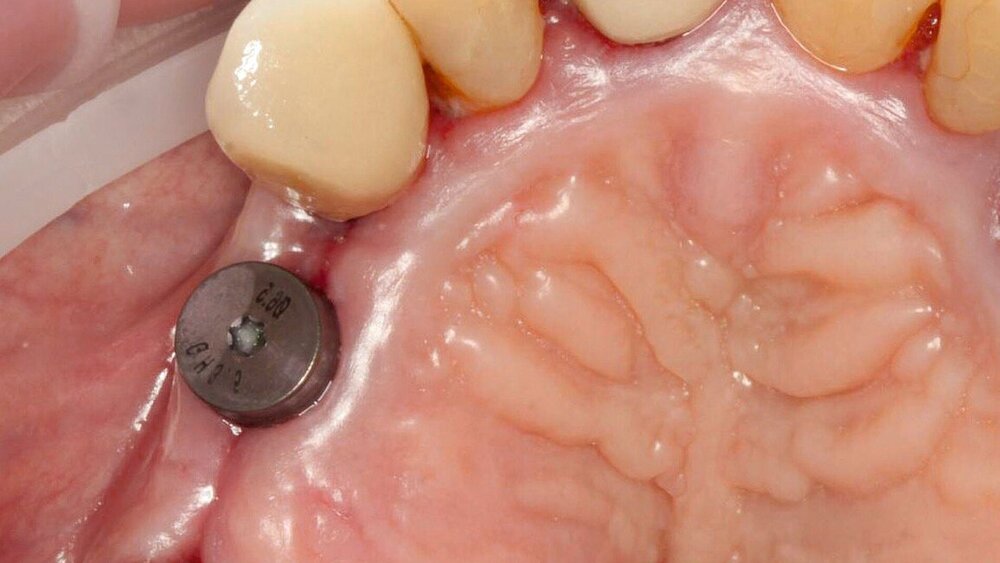

Inseriert wurden in 67,5 Prozent der Fälle Implantate der Firma Straumann („tissue level“) und zu 20,1 Prozent Implantate der Firma Thommen medical („Element“). Die Übrigen waren unterschiedliche, von überweisenden Kollegen gewünschte Fabrikate. Die meisten Implantate (46,1 Prozent) wurden mit einer Einzelkrone prothetisch versorgt. Die Verlustrate der Implantate während des Untersuchungszeitraums betrug 9,5 Prozent.